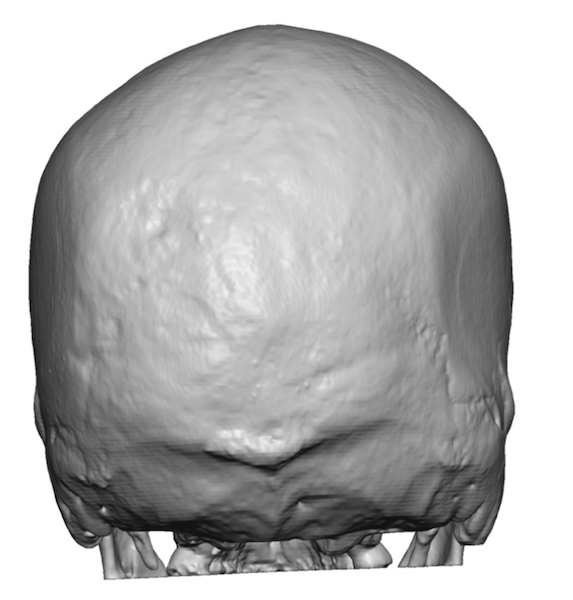

Desire to build up the flatter upper part of the back of his head.

Upper occipital skull augmentation using a custom skull implant.

Desire to build up the flatter upper part of the back of his head.

Upper occipital skull augmentation using a custom skull implant.